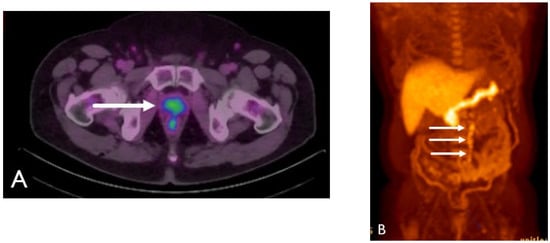

Detection of Loco-Regional Disease and Distant Metastases

1.9.3. Pearls and Pitfalls